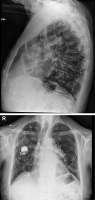

Thorax-Röntgen

Abbildung 3: Thorax-Röntgen